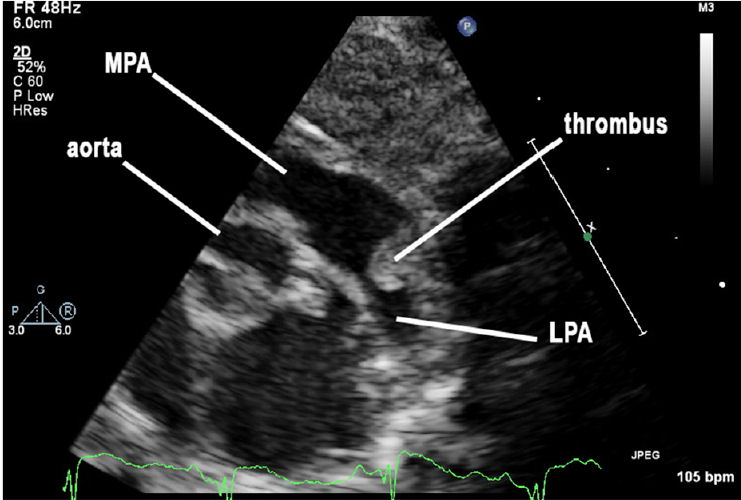

Un hallazgo incidental de trombo del ductus arterioso que se extiende a arteria pulmonar principal y arteria pulmonar izquierda se descubrió en la ecocardiografía (Figuras 1 y 2).

Figura 1.-

La vista paraesternal ecocardiográfica de eje corto muestra una imagen de corte

transversal del corazón. Aquí el trombo protuye desde conducto arterioso

permeable hacia arteria pulmonar principal (MPA) y arteria pulmonar izquierda (LPA).